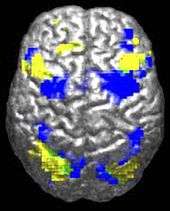

ASD-related patterns of low function and aberrant activation in the brain differ depending on whether the brain is doing social or nonsocial tasks.[94] In autism there is evidence for reduced functional connectivity of the default network, a large-scale brain network involved in social and emotional processing, with intact connectivity of the task-positive network, used in sustained attention and goal-directed thinking. In people with autism the two networks are not negatively correlated in time, suggesting an imbalance in toggling between the two networks, possibly reflecting a disturbance of self-referential thought.[95]

The underconnectivity theory of autism hypothesizes that autism is marked by underfunctioning high-level neural connections and synchronization, along with an excess of low-level processes.[96] Evidence for this theory has been found in functional neuroimaging studies on autistic individuals[37] and by a brainwave study that suggested that adults with ASD have local overconnectivity in the cortex and weak functional connections between the frontal lobe and the rest of the cortex.[97] Other evidence suggests the underconnectivity is mainly within each hemisphere of the cortex and that autism is a disorder of the association cortex.[98]

Functional connectivity studies have found both hypo- and hyper-connectivity in brains of people with autism. Hypo-connectivity seems to dominate, especially for interhemispheric and cortico-cortical functional connectivity.[102]